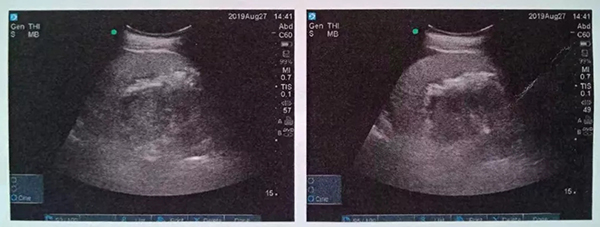

術(shù)中,泌尿外科郭駿博士精心設(shè)計(jì)手術(shù)通道,只在患者體表鉆出兩個(gè)0.5厘米的小洞,由于患者右側(cè)上位腎位置高,靠近肝臟和肺下葉,容易出現(xiàn)肝臟和肺的損傷,在B超的引導(dǎo)下精確穿刺腎結(jié)石的最高點(diǎn),逐級擴(kuò)張后建立皮腎通道。這時(shí)屢次“惹禍”的腎結(jié)石清楚的顯露在手術(shù)屏幕上,結(jié)石呈淺黃色,表面覆蓋淺褐色的膿苔,然后使用鈥激光將結(jié)石擊碎后取出。歷時(shí)一個(gè)半小時(shí),結(jié)石全部清除,手術(shù)結(jié)束。

術(shù)后CT,箭頭所指為腎結(jié)石被徹底清除

三日后,曾奶奶病情逐漸穩(wěn)定,各項(xiàng)感染指標(biāo)逐漸恢復(fù)正常,復(fù)查CT顯示腎結(jié)石已經(jīng)被完全清除,現(xiàn)已康復(fù)出院。就此,困擾曾奶奶多年,反復(fù)感染差點(diǎn)致命的腎結(jié)石頑疾被徹底治愈。曾奶奶全家人對于愛康醫(yī)院泌尿外科專家高超的碎石取石手術(shù)技藝更是贊許有加,對泌尿外科團(tuán)隊(duì)的工作給予衷心感謝和高度評價(jià)。